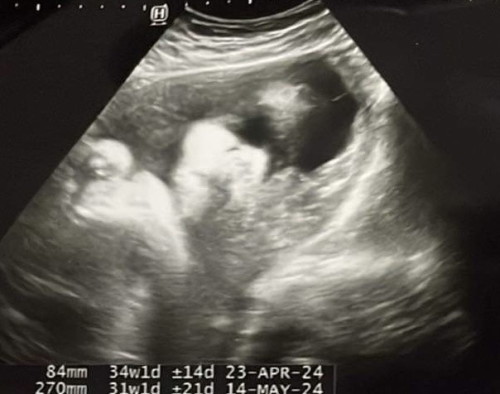

จากในรูปน้องมีความเสี่ยงจะเป็นปากแหว่งเพดานโหว่ไหมคะ

ถ้าหมอไม่แจ้งก็อย่าคิดมากค่ะถ้าอยากสบายใจแนะนำซาว4มิติค่ะ

ภาพไม่ชัดค่ะ